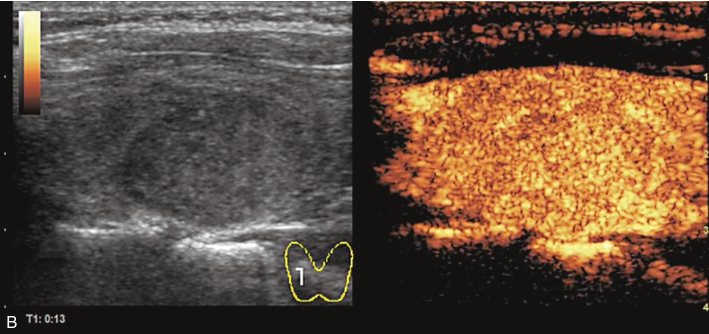

女性,56岁,体检发现甲状腺结节1周。

甲状腺右叶中上部见一低回声结节,大小约0.7cm×0.7cm×0.8cm,边界清楚,形态尚规则,内可见少许点状强回声。CDFI示结节内及周边可见较丰富血流信号,见图1-9-5。

图1-9-5 甲状腺髓样癌常规超声声像图

A.甲状腺右叶结节横切面;B.甲状腺右叶结节纵切面;C.甲状腺右叶结节CDFI血流图

甲状腺右叶上部结节超声造影后早于周围组织开始出现增强,达峰时呈偏低增强表现,边界不清,范围未见明显扩大,之后快速消退,晚期呈明显低增强,结节旁甲状腺被膜增强完整,见图1-9-6、ER1-9-3。

造影后结节内呈不均匀偏低增强表现,增强边界不清,增强晚期快速消退。

髓样癌体积较小时与乳头状癌的鉴别存在困难,内部丰富血流是髓样癌的主要特点,超声造影表现为中等偏低增强,与乳头状癌明显的低增强表现有别。

常规超声表现类似,超声造影后腺瘤常边界清楚,周边可见规则环状增强。实验室检查中降钙素、CEA升高对于髓样癌的确诊具有重要意义。